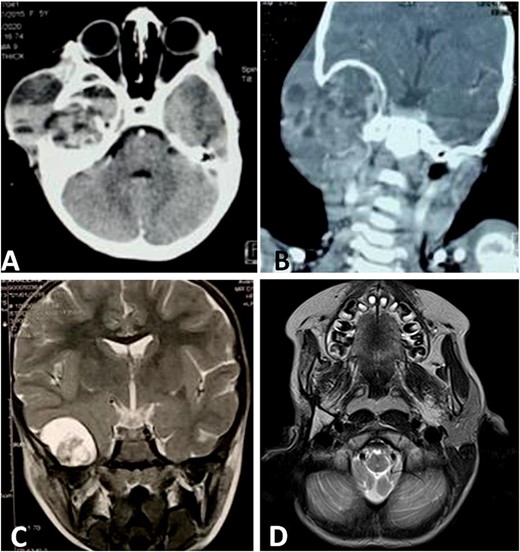

We noted an aggravation of symptoms with malignant otitis, progressive facial paralysis, retro-auricular swilling (Fig. 1A) and appearance of neurological signs. The CT scan revealed a significant osteolysis of the petrous bone, mastoid and temporal bone with homolateral meningeal and cerebral extension. This suggested a malignant process (Fig. 2).

CT scan shows a cystic process of the middle ear cavities with a significant osteolysis of the petrous bone, mastoid and temporal bone (A) with extension to parotid region (B) and homolateral meninge and brain (C). Follow-up MRI shows no sign of recurrences (D).

Then, the patient underwent total surgical resection preceded by chemotherapy. At surgery, the tumor was noted to be located in the petrous bone itself and did not arise from the underlying dura. Therefore, the underlying dura mater was preserved. The reconstruction was made by filling with abdominal fat and biological glue, with a good result (Fig. 1B and C). The follow-up magnetic resonance imaging (MRI) showed no sign of recurrences with 3 years survival (Fig. 2D).